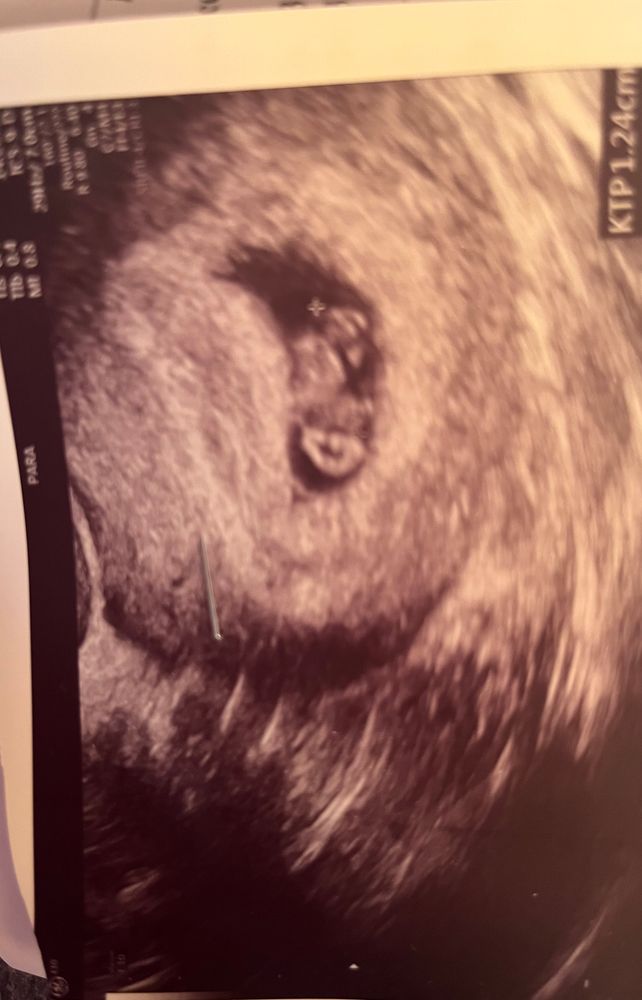

Наша 8-я неделя